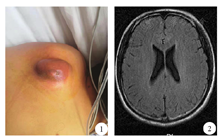

患者男性,28岁,因"发热3 d,意识模糊1 d"于2019年4月6日入院。3 d前患者无明显原因突然发热,体温37.5~38.8 ℃,就诊于当地医院,服用"氨咖黄敏胶囊、阿莫西林胶囊"等药物治疗,发热无缓解。1 d前患者逐渐出现反应迟钝、睡眠增多、意识模糊,并逐渐加重,以"中枢神经系统感染查因"收入神经内科。患者否认有鼻塞、流涕、咽痛、咳嗽、腹痛、腹泻等呼吸系统及消化系统感染病史。入院体检:体温38.5 ℃,心率98次/min,呼吸21次/min,血压126/80 mmHg(1 mmHg=0.133 kPa)。后颈部正中处有一5 cm×6 cm大小包块,局部皮肤发红、破溃,皮温较高,触之有波动感(图1)。神经专科检查:意识模糊,精神差,答非所问,高级智能异常,四肢肌力、肌张力正常,四肢腱反射正常,双侧病理征阴性,颈强直,颌距胸4横指,双侧克尼格征(+),双侧布鲁斯基津征(+)。辅助检查:血常规:白细胞16.78×109/L,中性粒细胞计数15.48×109/L;降钙素原19.75 ng/mL;腰椎穿刺示颅内压320 mmHg;脑脊液常规:外观呈黄色,浑浊,潘氏试验阳性,白细胞8120×106/L,多核为主;脑脊液生化:蛋白3163.5 mg/L,葡萄糖0.04 mmol/L,氯115.8 mmol/L;肝肾功、凝血功能、电解质、风湿免疫等检测项目均正常,脑脊液及血细菌培养未发现致病菌;头颅MRI未见明显异常,脑室无扩大(图2);颈胸椎MRI示C7、T1、T2棘突缺如,脑脊液囊向后突出,到达皮肤表层,脊髓神经根和脊膜等组织疝出,脊髓软化或脊髓空洞形成,脊髓神经根从背侧延伸至脊膜壁(图3);腰椎MRI示L4/5、L5/S1椎间盘突出,圆锥位置未下降,脊髓、马尾及终丝未见到明显牵拉(图4)。诊断:细菌性脑膜炎;颈胸段脊髓脊膜膨出。